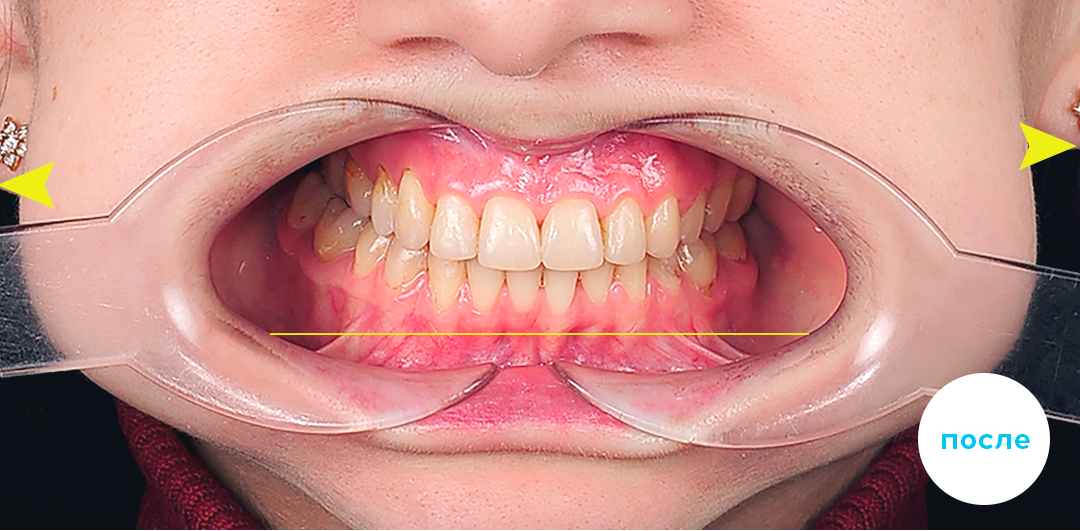

Работы специалиста